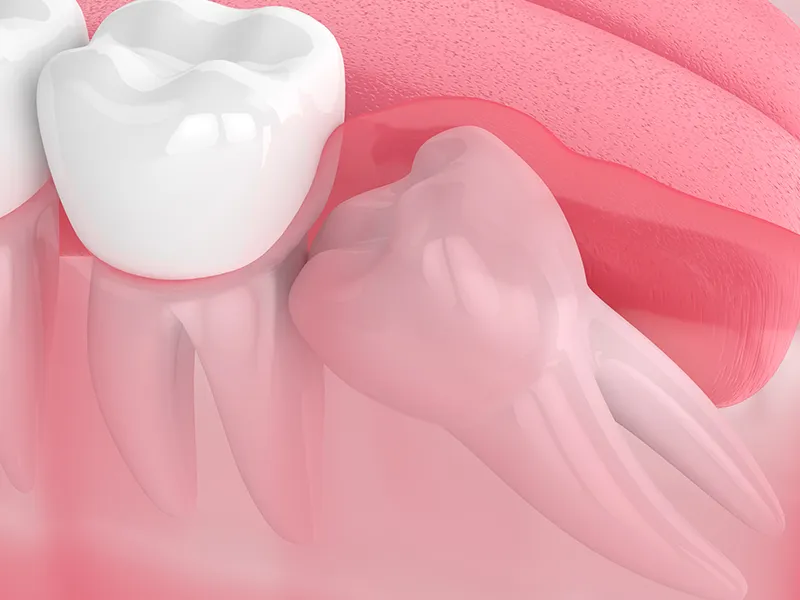

Impaction: When wisdom teeth lack the space to fully emerge, they may become impacted by growing at an angle, getting trapped under the gum line, or pressing against adjacent teeth. Impacted wisdom teeth can cause pain, swelling, and damage to neighbouring teeth.

For our ancestors, wisdom teeth played a crucial role in chewing and grinding tough, unprocessed foods like roots, meats, and nuts. However, modern diets are much softer, and human jaws have gradually evolved to be smaller. Because of this reduced jaw space, wisdom teeth often don’t have enough room to emerge properly. This lack of space can lead to the teeth becoming impacted (trapped beneath the gums) or growing in at awkward angles, causing discomfort and a range of dental problems.